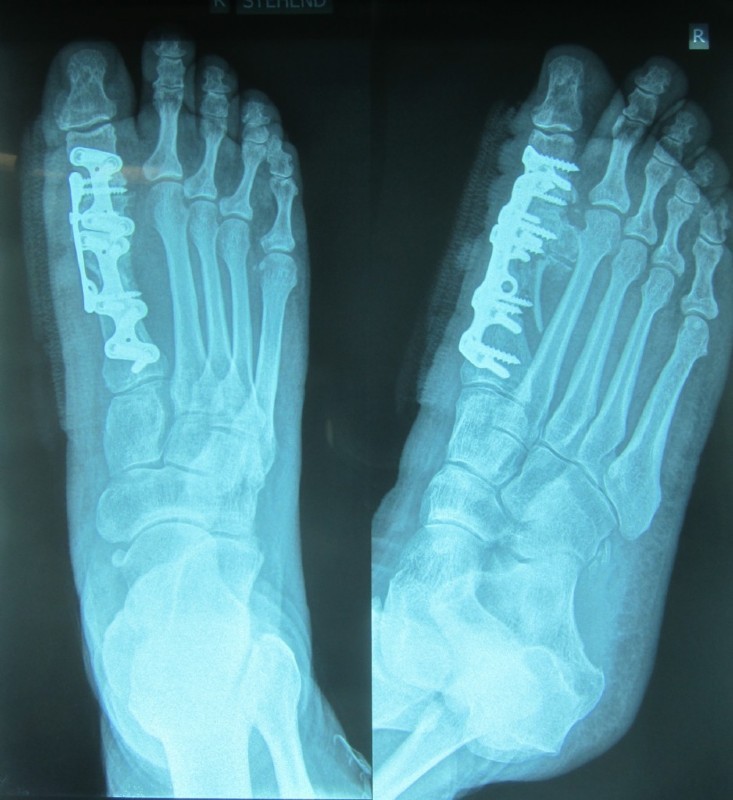

Hier ein Beispiel einer Versteifung mit oben am Knochen liegender Platte und einer Längsschraube zur weiteren Stabilisierung.

Versteifung

Das Gelenk wurde vom Restknorpel und von verdickten Knochenanteilen (Arthrosefolge) befreit und die Gelenkpartner in die Funktionsstellung gebracht, also der 2. Zehe parallel gestellt und etwa 15 Grad (bei Männern) bis 20 Grad (bei Frauen) gestreckt (aufgestellt). Damit kann man nach Abheilung einwandfrei gehen.

Unmittelbar nach der Operation ist das Gehen mit dem Entlastungsschuh (für 6 bis 8 Wochen) gut möglich. Häufig kann die Platte belassen werden, manchmal stört sie, dann wird das Metall in einem zweiten kleinen Eingriff entfernt.

Unten sehen Sie eine zartere Platte, die wir jetzt zum Einsatz bringen:

Die modernen Platten sind sehr zart und doch fest. Zur "Aufbiegestabilisierung" wird auch hier eine Längsschraube fußsohlennahe eingeschraubt. Dadurch entsteht eine Rahmenkonstruktion.

Der Pfeil zeigt die Stelle, an der früher das erkrankte (durch Arthrose zerstörte) Gelenk war. Statt dessen befindet sich dort jetzt nach Abheilung fester Knochen. Das Gelenk ist also steif und das OP-Ziel wurde erreicht. Der Fuß kann nun völlig schmerzfrei abgerollt und voll belastet werden.